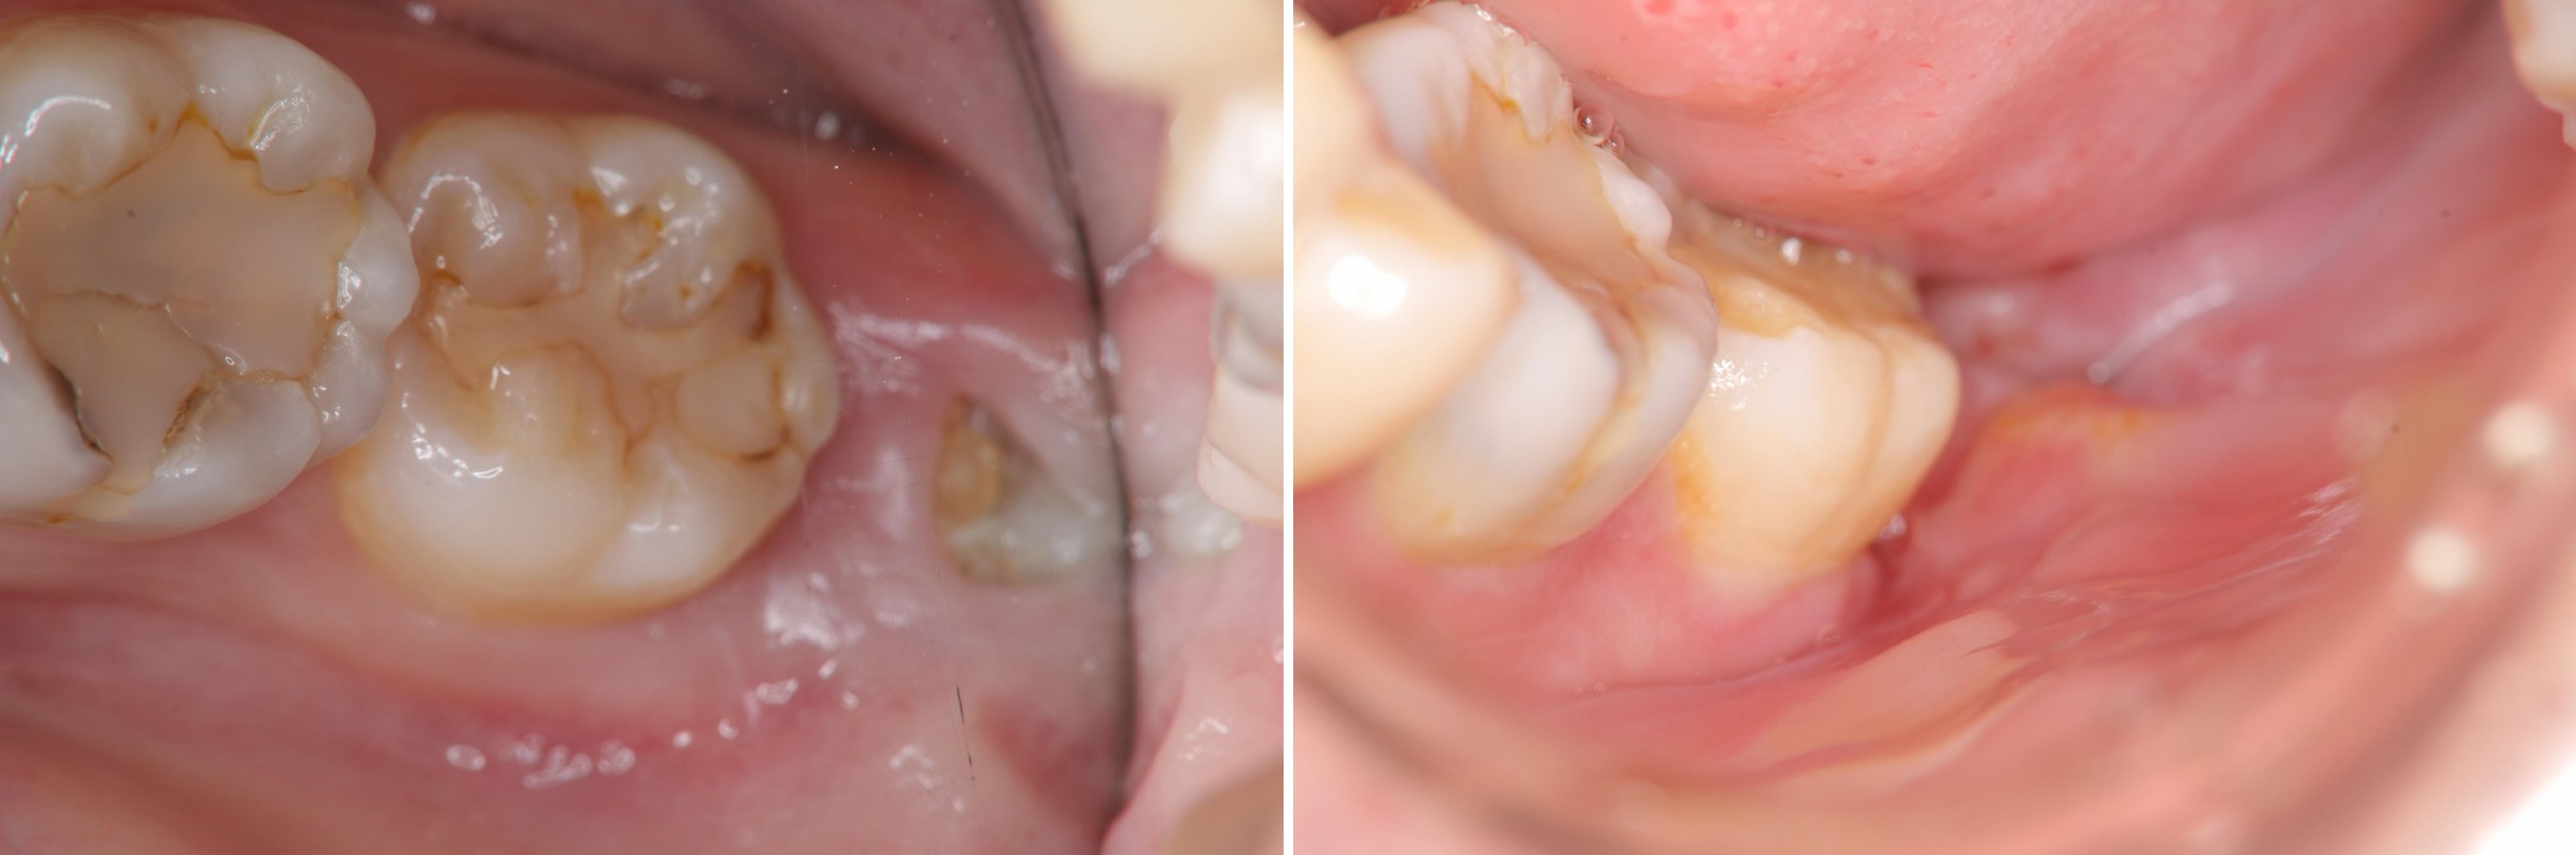

牙髓-牙周-膺復合併症-蛀牙-#3637

根管治療

牙髓/牙周/膺復合併症